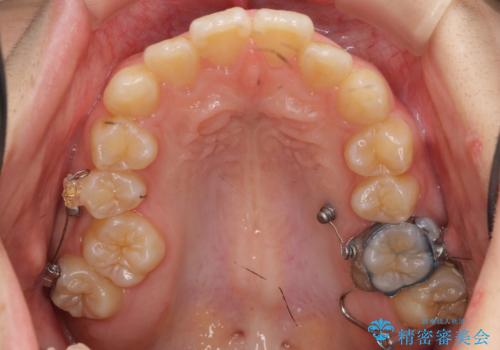

インビザライン治療は主に奥歯のかみ合わせが大きな問題がない場合は特に問題なく終了しますが、今回のケースのように奥歯のかみ合わせが悪い場合、しっかり治らないことがあります。

患者様が気づかない範囲で妥協して終わるということをせず、しっかり奥歯に部分矯正を用いて大きな問題を解決してからインビザライン治療に入りました。

奥歯のワイヤー部分矯正は位置的に人から気づかれることはないと思います。